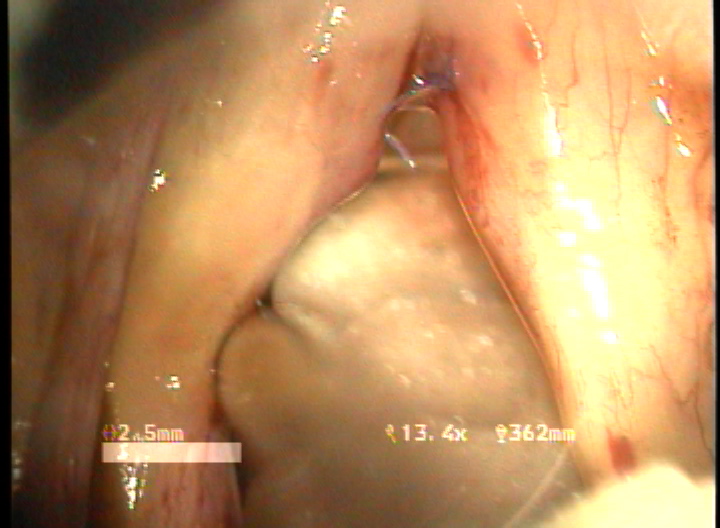

목적 : 전성문횡격막(anterior glottic web)은 선천성이나 수술과 같은 이차적인 원인에 의해서 발생되는 난치성 후두질환이다. 또한 기존의 치료방법으로는 음성개선의 효과가 매우 낮은 결과를 얻고 있다. 이에 음성의 보존과 함께 일차적 시술로서 치료가 가능한 double rotation microflap 을 이용한 새로운 술식을 보고하며, 이술식의 치료결과와 음성학적 개선을 알아보고자 하였다.

방법 : 2006년 1월 부터 2007년 12월 까지 예송이비인후과에서 전성문횡격막으로 진단되어 double rotational microflap laryngoplasty를 시행받고 1년간 장기추적이 가능하였던 6명의 환자를 대상으로 후향적 분석을 시행하였다. 원인적인 요인과 동반질환으로는 후두유두종 술후 합병증 4례, 후두외상 1례, 폴립양성대 1례 였다. 남녀 각각 3례였으며, 평균연령은 39세 였다. 추적기간은 21.5 개월이었다. 술 후 2개월과 6개월에 음성개선에 대한 주관적인 음성평가를 시행하였으며, 음성분석검사와 후두스트로보스코피 검사를 통하여 객관적인 음성평가와 성대점막파동의 변화를 관찰하였다. 통계적 유의성은 Wilcoxon Signed Ranks Test로 검정하였다.

결과 : 음성개선에 대한 주관적인 평가로서 수술전 Voice Handicap Index는 평균 19.7 에서 술후 11.5로 감소하였다. 공기역학적인검사상 성문하압은 5.5에서 4.5로 감소되었으며, 최대발성시간 13.7에서 16.1로 증가되었다. 음성분석검사상 sPPQ, sAPQ, NHR, SPI, DSH가 모두 통계학적으로 유의하게 감소하였다. 후두스토로보스코피검사상 모든 례에서 재발의 징후없이 성대점막파동의 의미있는 호전이 나타났다. 합병증으로 1례에서 염증성 육아종형성이 관찰되었으나 미세피판의 괴사나 탈락은 관찰되지 않았다.

결론 : 전성문횡격막의 새로운 수술방법으로서 double rotational microflap laryngoplasty는 일차수술로 만족스러운 음성학적 치료결과를 얻을 수 있는 매우 유용한 술식이라 사료된다.